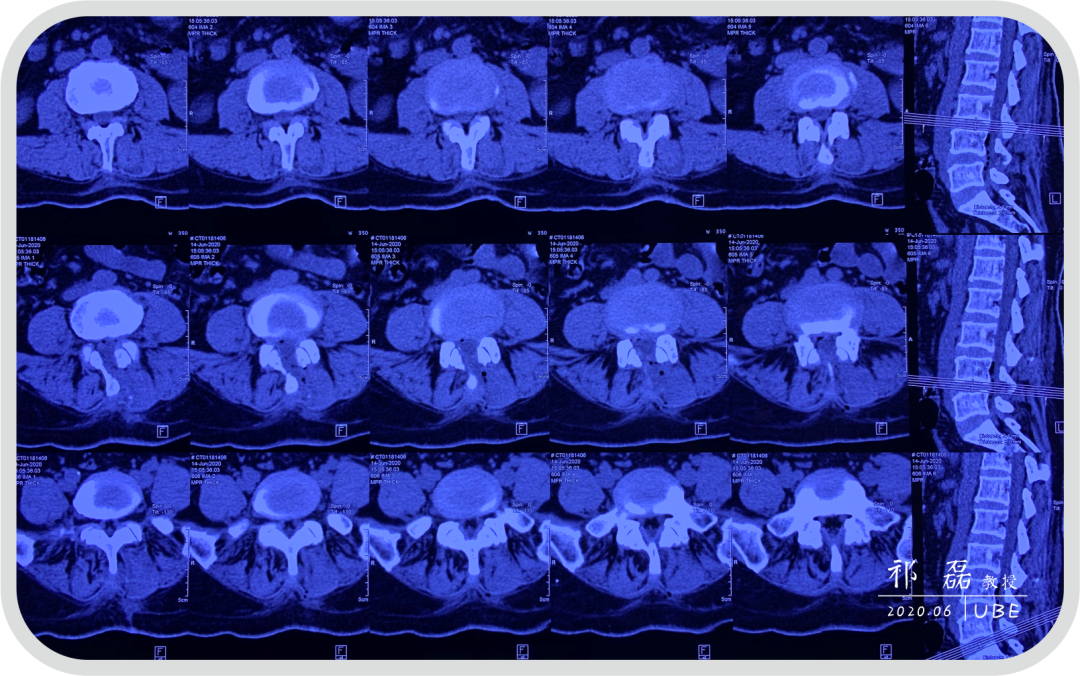

患者:吴某,女,53岁,腰痛及双下肢疼痛麻木5年余,加重1月余,间歇性跛行约200米。于近日入我院查体,下腰椎棘突及椎旁肌深压痛,双下肢感觉运动正常。双侧直腿抬高试验(-),双侧踝反射(-),入院诊断为:腰椎管狭窄症。

图2:腰椎CT